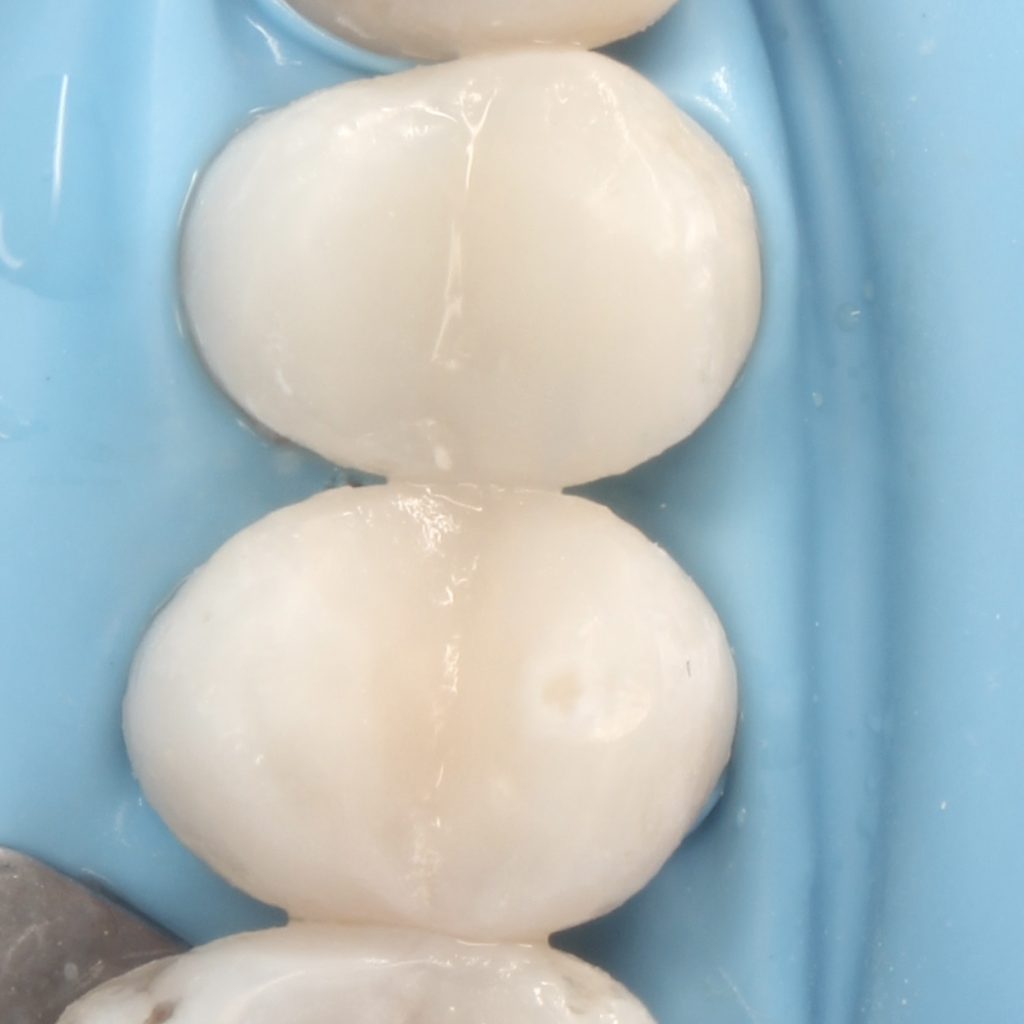

A 22 years old patient came to the clinic suffering from severe spontaneous pain. The diagnosis was acute irreversible pulpitis. The use of CDD is crucial here to ensure the CRE. After finishing endodontic treatment we used polyethylene fibers to enhance the bond strength and the strength of the tooth. Then the use of glass fibers (ever X composite) as a dentin replacement material before the final layer. After finishing. Polishing protocol with eve twist was done to gain the final polish